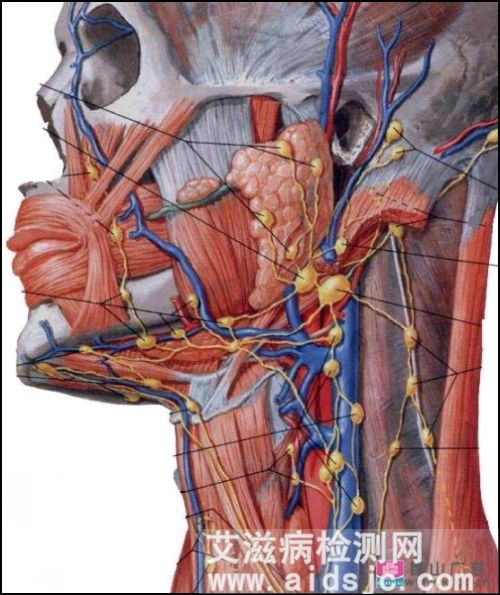

艾滋病初期淋巴结肿大位置图,会痛吗_艾滋病初期症状_艾测网

颈部淋巴结肿大_图片_互动百科

双下颌淋巴结肿大,最大的约有2*1cm大小,无痛,质中,表面光滑,活动性良好。